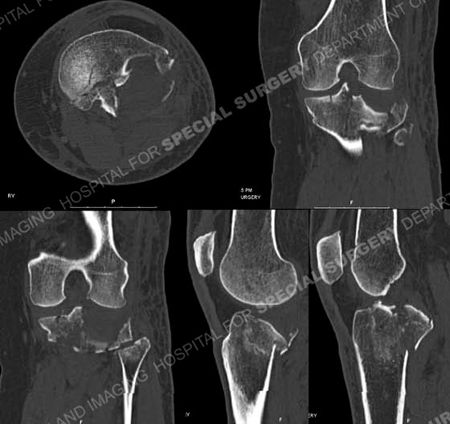

Di Eropa sendiri bidang kesehatan telah dipakai sejak tahun 1800-an dan berkembang sangat pesat di masa sekarang ini. Contoh dalam bidang kesehatan yang akan saya bahas adalah Computer Tomography (CT) Scan

CT Scan adalah sebuah alat untuk mengecek kondisi pasien dengan menembakkan sinar X yang dihasilkan oleh CT Scan. Bagaimana cara kerjanya? Menarik, yuk kita bahas.

Gambar CT Scan (Google)

Berbeda dengan sinar X yang biasa digunakan dalam tabung, CT Scan memusatkan keluaran sinar X di antara bentuk bulat seperti donat tersebut yang diberi nama Gantry. Di waktu pasien melakukan CT Scan, di awalnya dia akan tiduran di kasur yang disediakan dan perlahan-lahan kasur tersebut bergerak melewati Gantry, bersamaan dengan itu sinar X akan langsung ditembakkan untuk mengitari pasien. CT Scan menggunakan pendeteksi sinar X dibandingkan dengan film, yang terletak berbeda dengan sumber sinar X berasal. Setelah proses pemindaian selesai maka pendeteksi tersebut mengirimkan datanya ke komputer

Contoh hasil dari CT Scan (Google) - Bidang Pertanian.